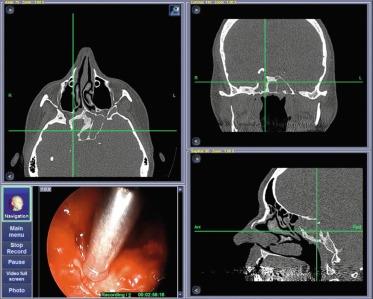

• System accuracy is liable to drift during the procedure and needs to be regularly checked against straightforward landmarks, especially at start of surgery, and further periodic checks should be made throughout ( Figure 3.1 ), as accuracy can vary within a given working volume according to a complex distribution function [ ]. When the displayed position differs markedly from that estimated by the operator, the discrepancy should be resolved by checking, for example, bordering landmarks. These checks enable not only safe operating, but also an estimation of the value and limitations of the equipment. They also encourage a certain humility and willingness to keep on learning anatomy, no matter how experienced you may be.

Figure 3.1, Accuracy check during navigation.